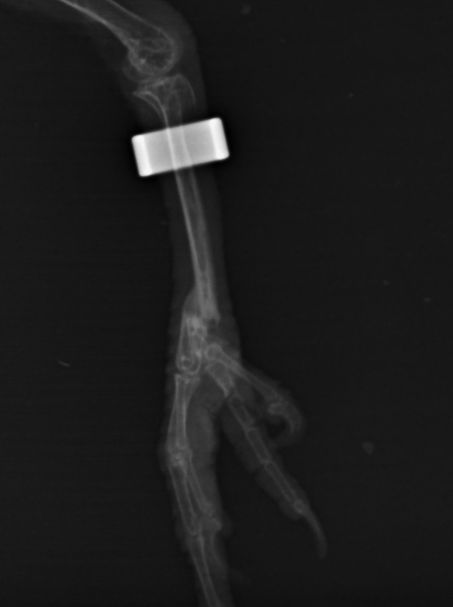

Une petite nouvelle, mais il faut bien regarder la photo.

- 178.jpg (10.42 Kio) Vu 27617 fois

Pas très visible mais je crois que pour lui, la saison de ski est foutue.

Heureusement, j'ai été très bien accueilli à l'ENV de Toulouse.

Donc en cage hôpital, avec un 'plâtre' pour 3 semaines.

Pour l'instant, le petit Touraco semble OK.